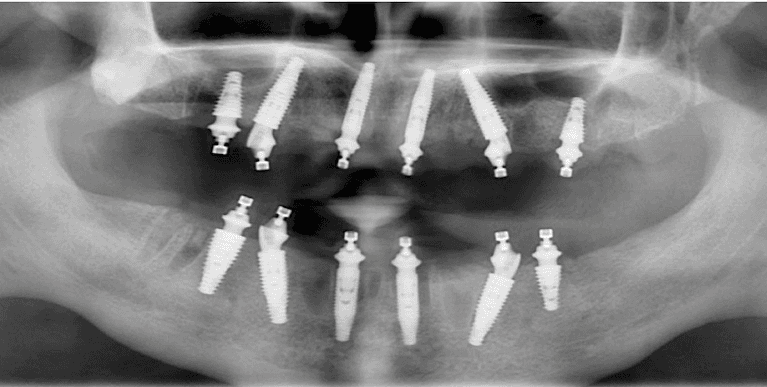

Upper & Lower, All on 4 fixed implant teeth with finals. Patient went home with temp fixed teeth the same day.